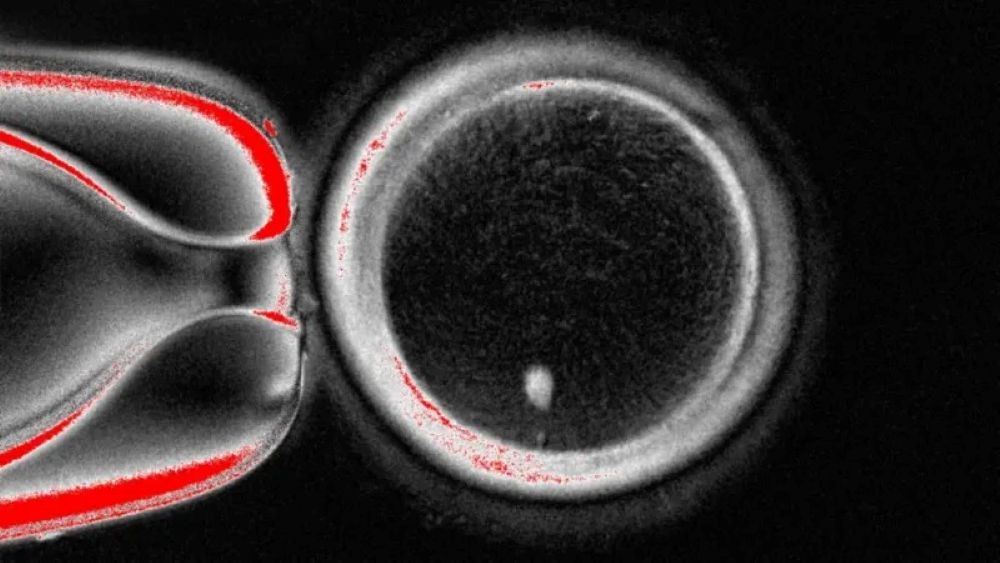

WASHINGTON: Pasukan ssaintis di Amerika Syarikat (AS) berjaya menghasilkan embrio manusia peringkat awal dengan memanipulasi asid deoksiribonukleik (DNA) yang diambil daripada sel kulit manusia sebelum disenyawakan dengan sperma. Teknik ini berpotensi mengatasi masalah ketidaksuburan akibat faktor usia atau penyakit dan berpotensi membolehkan pasangan sejenis mempunyai anak yang berkongsi hubungan genetik dengan mereka. Pasukan penyelidik dari Universiti Sains dan Kesihatan Oregon menggunakan teknik mengambil nukleus yang menyimpan keseluruhan kod genetik diperlukan…